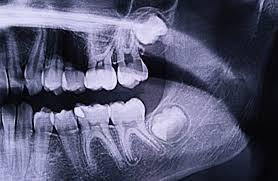

1. Rontgen Gigi

Dokter akan meminta kamu melakukan rontgen gigi di laboratorium radiologi yang memenuhi standar. Pemeriksaan ini bertujuan untuk melihat kondisi gigi secara menyeluruh, termasuk posisi gigi dan saraf di sekitarnya.

Dengan hasil rontgen, dokter dapat menentukan letak gigi yang perlu dicabut tanpa membahayakan saraf lainnya.